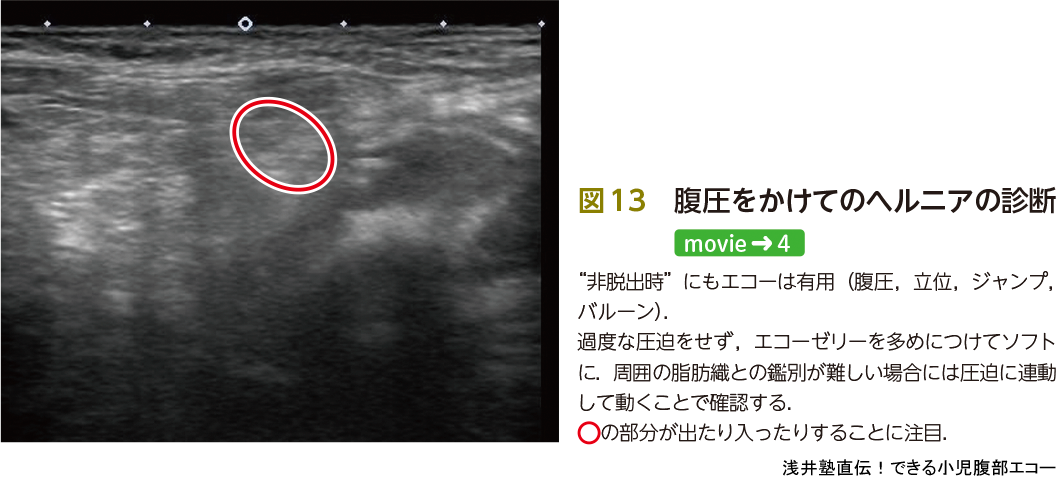

浅井塾直伝!できる小児腹部エコー〜描出・診断・治療まで「いい

小児消化管超音波診断アトラス

診断と治療社

玉井浩

2005/04/01

4787811975

9784787811974